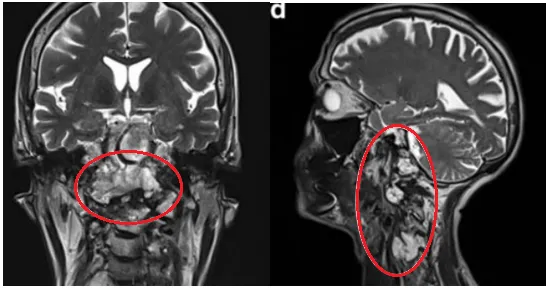

2019年初随访MRI,显示脊索瘤复发,颅颈交界区脊索瘤病变大小为51.3×74.3×25.9 mm,脊索瘤已经引起C2椎体病理性骨折及C1水平脊髓压迫,伴随C1右侧方、C1前后弓、C2椎体侵犯,齿状突后移和C1水平的侧向移位(图6)。肿瘤侵袭上三分之一的髁突和斜坡水平(图6a-c)。肿瘤侵袭延伸至C5-C6水平,在椎前间隙浸润延伸,并压迫C5和C6神经根,并包裹椎动脉椎动脉的V2段(图6d)。临床检查显示神经反射亢进和Lhermite征阳性。

▼图a-b术前MR显示颅颈交界区较大脊索瘤,51.3×74.3×25.9 mm大小,浸润性生长。

▼图显示脊索瘤向周边浸润生长,下至C5-C6水平的脊髓瘤侵犯浸润。图片